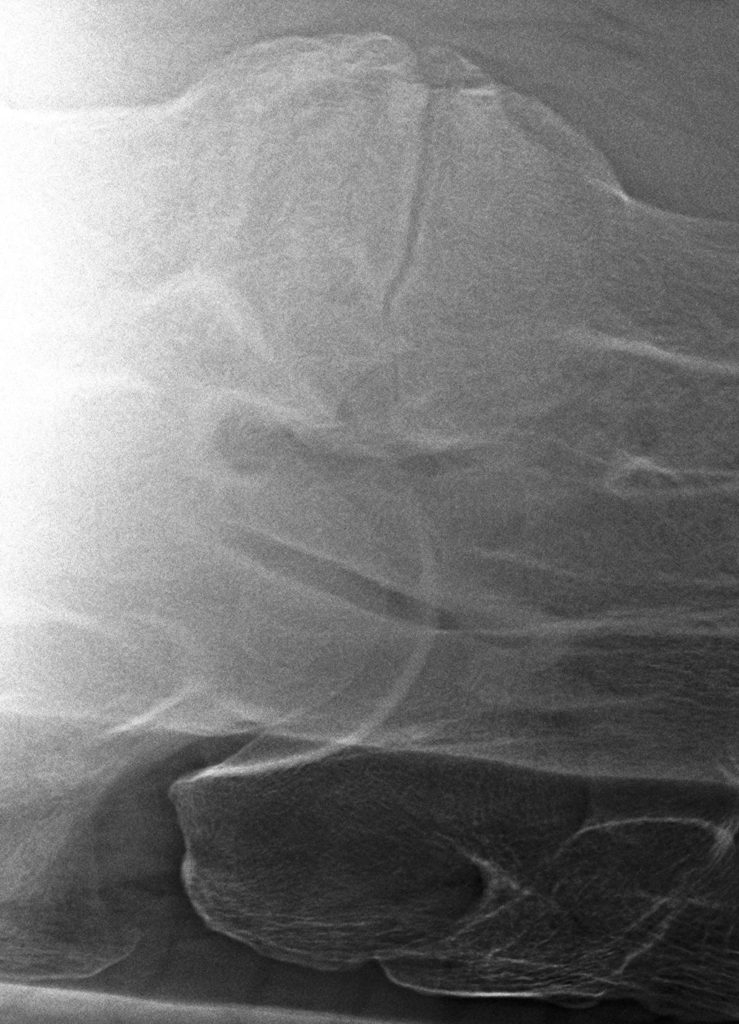

Het klinische onderzoek kunnen we aanvullen met beeldvorming. Op röntgenopnamen kunnen we de facetgewrichten van de gehele hals beoordelen, bij een zijdelingse opname zien we echter beide facetgewrichten over elkaar heen geprojecteerd. Om deze apart te kunnen beoordelen kunnen we “schuine” foto’s maken, ofwel uitprojecties.

Links: Facetgewricht röntgen

Rechts: Uitprojectie facetgewricht

Facetgewricht röntgen

Uitprojectie facetgewricht